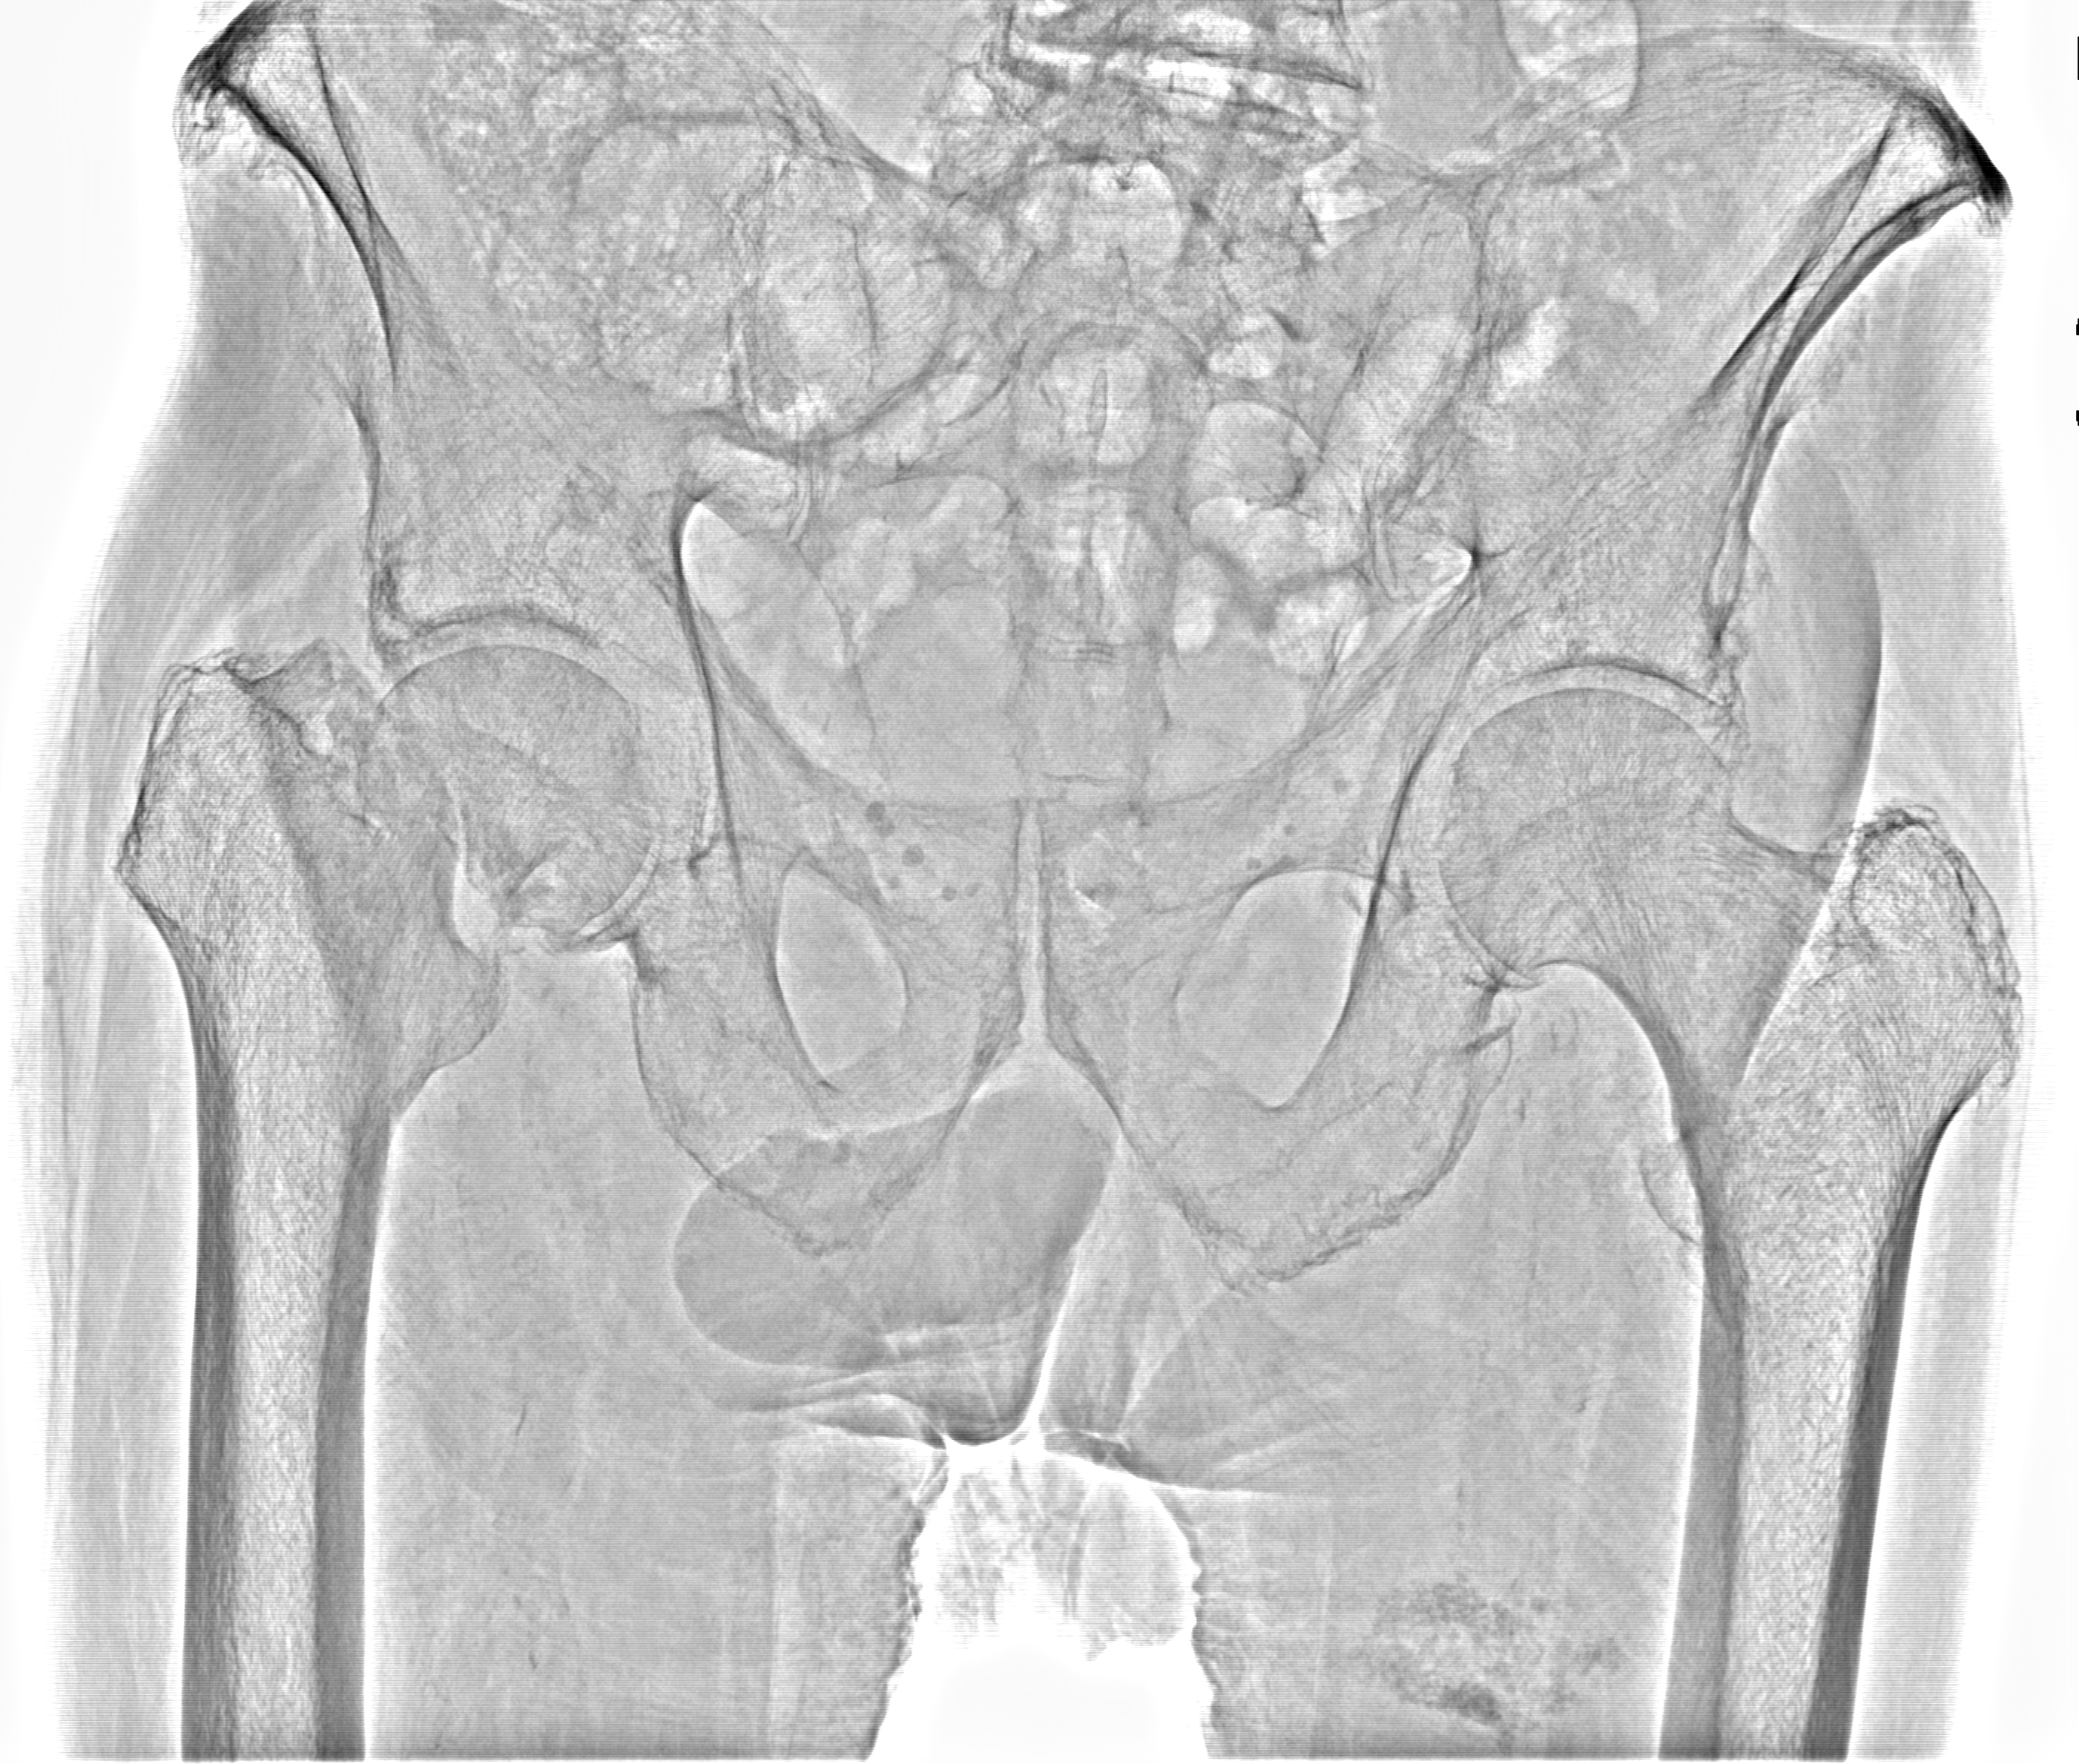

Перелом шейки бедра от 27042021

Рентген на дому: по вашему адресу приезжает врач-рентгенолог, травматолог-ортопед с мобильным рентгеновским аппаратом, проводит диагностику травмы или заболевания, делает необходимые рентгенограммы, дает рекомендации по дальнейшему лечению. Получить качественные снимки в домашних условиях возможно благодаря уникальной методике, разработанной МосРентген Центром для института  Склифосовского